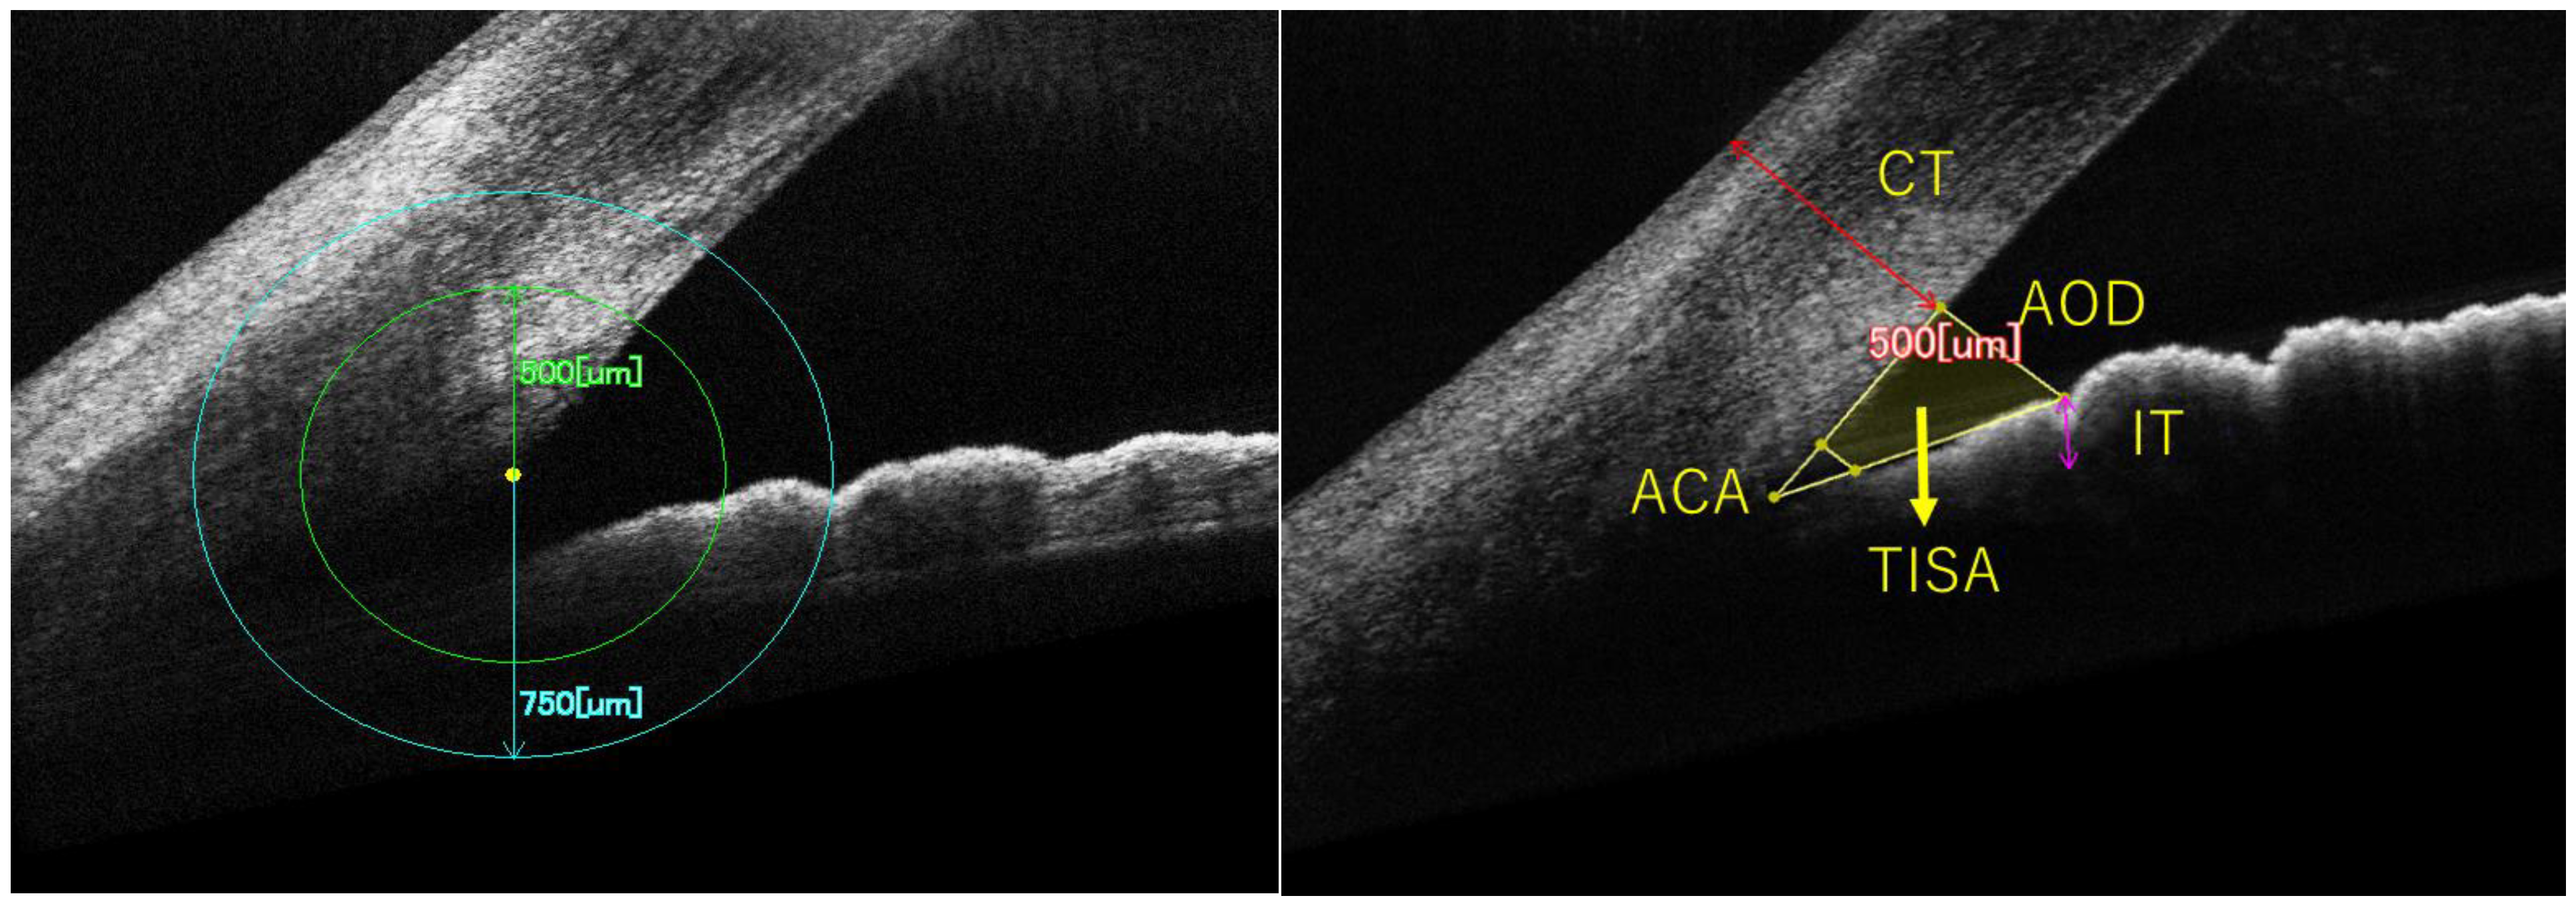

| Parameters | SE (Correlation Coefficient, p-Value) | AL (Correlation Coefficient, p-Value) | Uncorrected logMAR (Correlation Coefficient, p-Value) |

|---|---|---|---|

| ACA500μm | −0.19 (<0.001) | 0.22 (<0.001) | 0.16 (<0.001) |

| ACA750μm | −0.24 (<0.001) | 0.26 (<0.001) | 0.19 (<0.001) |

| AOD500μm | −0.19 (<0.001) | 0.25 (<0.001) | 0.18 (<0.001) |

| AOD750μm | −0.24 (<0.001) | 0.30 (<0.001) | 0.21 (<0.001) |

| TISA500μm | −0.17 (<0.001) | 0.24 (<0.001) | 0.16 (<0.001) |

| TISA750μm | −0.23 (<0.001) | 0.29 (<0.001) | 0.19 (<0.001) |

| PCT500μm | 0.05 (0.22) | 0.11 (0.004) | −0.06 (0.12) |

| PCT750μm | 0.08 (0.04) | 0.11 (0.006) | −0.08 (0.04) |

| PIT500μm | −0.01 (0.76) | 0.05 (0.21) | −0.03 (0.41) |

| PIT750μm | −0.01 (0.83) | 0.04 (0.35) | −0.02 (0.55) |